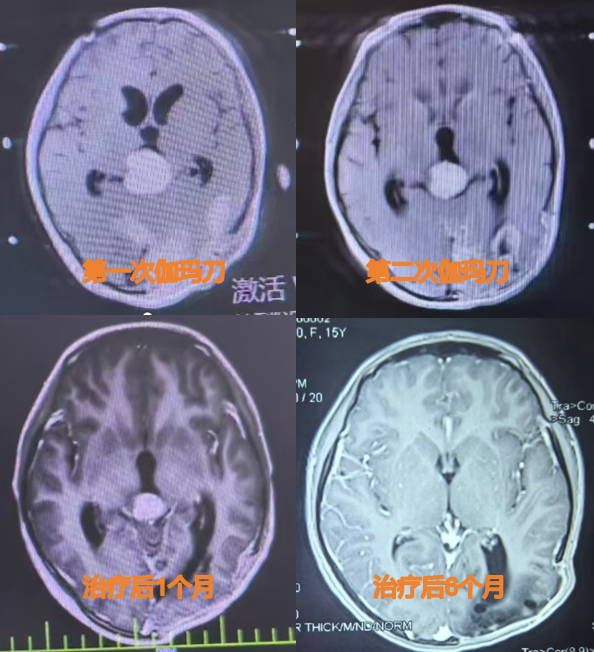

为缩短单次治疗时间,保证小汪安全,龚飞龙决定用伽玛刀分两次放射治疗,中间间隔5天。幸运的是,首次伽马刀放射治疗后,小汪的检查结果显示其脑肿瘤体积缩小了50%。两次伽马刀放射治疗后,脑肿瘤体积缩小了80%。

目前,术后7个月的小汪,病情已得到控制,眼球活动完全恢复正常,视力正常。(受访者供图)